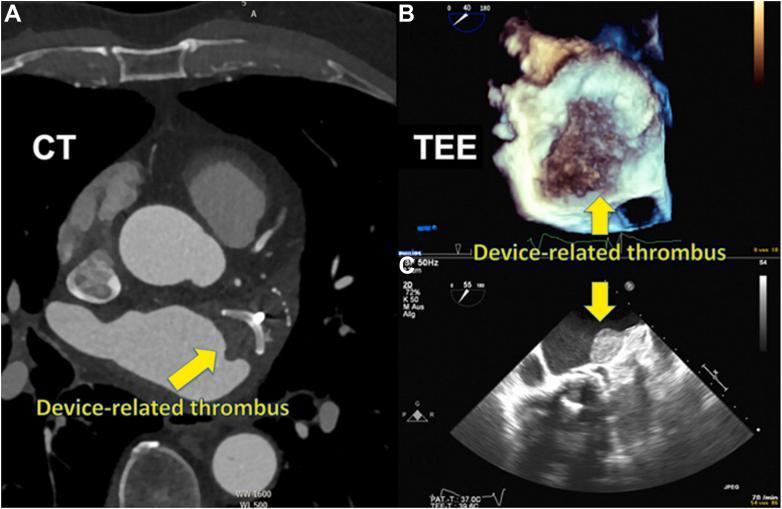

The left atrial appendage (LAA) is a complex structure with unknown physiologic function protruding from the main body of the left atrium. In patients with atrial fibrillation, the left atrium does not contract effectively. Insufficient atrial and LAA contractility predisposes the LAA morphology to hemostasis and thrombus formation, leading to an increased risk of cardioembolic events. Oral anticoagulation therapies are the mainstay of stroke prevention options for patients; however, not all patients are candidates for long-term oral anticoagulation. Percutaneous occlusion devices are an attractive alternative to long-term anticoagulation therapy, although they are not without limitations, such as peri-implant leakage and device-related thrombosis. Although efforts have been made to reduce these risks, significant interpatient heterogeneity inevitably yields some degree of device-anatomy mismatch that is difficult to resolve using current devices and can ultimately lead to insufficient occlusion and poor patient outcomes. In this state-of-the-art review, we evaluated the anatomy of the LAA as well as the current pathophysiologic understanding and stroke prevention strategies used in the management of the risk of stroke associated with atrial fibrillation. We highlighted recent advances in computed tomography imaging, preprocedural planning, computational modeling, and novel additive manufacturing techniques, which represent the tools needed for a paradigm shift toward patient-centric LAA occlusion. Together, we envisage that these techniques will facilitate a pipeline from the imaging of patient anatomy to patient-specific computational and bench-top models that enable customized, data-driven approaches for LAA occlusion that are engineered specifically to meet each patient's unique needs.

左心耳(LAA)是从左心房主体突出的具有未知生理功能的复杂结构。在房颤患者中,左心房不能有效收缩。心房和左心耳收缩力不足使左心耳形态易于形成止血和血栓,导致心脏栓塞事件风险增加。口服抗凝治疗是患者预防中风的主要选择;然而,并非所有患者都适合长期口服抗凝治疗。经皮封堵装置是长期抗凝治疗的一种有吸引力的替代方法,尽管它们并非没有局限性,如植入周围渗漏和与装置相关的血栓形成。尽管已努力降低这些风险,但患者间显著的异质性不可避免地产生一定程度的装置-解剖结构不匹配,使用当前装置难以解决,最终可能导致封堵不足和患者预后不良。在这篇最新综述中,我们评估了左心耳的解剖结构以及当前对与房颤相关的中风风险管理中使用的病理生理学理解和中风预防策略。我们强调了计算机断层扫描成像、术前规划、计算建模和新型增材制造技术的最新进展,这些代表了向以患者为中心的左心耳封堵范式转变所需的工具。我们共同设想,这些技术将促进从患者解剖结构成像到患者特异性计算和台式模型的流程,从而实现专门为满足每个患者独特需求而设计的定制化、数据驱动的左心耳封堵方法。